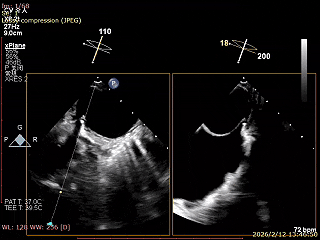

二尖瓣术前评估

复查TTE及TEE检查进一步评估二尖瓣情况。明确为AFMR,二尖瓣功能性反流,2区瓣叶运动,重度FMR(3+),肺静脉逆向血流;2区后叶长度13 mm,2区前叶长度20mm,AP径37mm,瓣口面积4.08cm²,房间隔高度4.5cm,瓣叶无钙化,二尖瓣瓣膜条件适合行TEER手术。

术前Bicom

二尖瓣2区功能性反流

二尖瓣三维视图

2区彩色血流